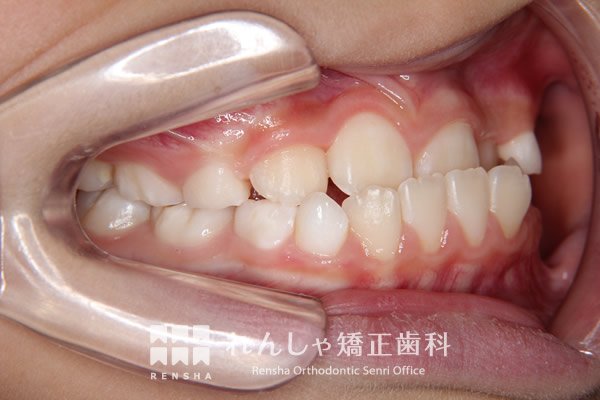

中高生

永久歯列はほぼ完成してしますが、歯列を側方だけでなく後方へも拡大し、埋まっていた右上奥歯を引っ張り出しています。

| 主訴 | 埋まったままでてこない歯がある |

|---|---|

| 診断名 | Angle Class II 小臼歯の埋伏と叢生を伴う上顎前突 |

| 初診時年齢 | 13歳5か月 |

| 装置名 | マルチブラケット装置 |

| 抜歯非抜歯 | 非抜歯 |

| 治療期間 | 2年3か月 |

| 費用の目安 | 約82万円+消費税(検査料金、都度の処置費用等も合わせた総額) |

| リスク副作用 | 歯の移動に伴う軽微な歯根吸収、歯槽骨吸収、歯肉退縮(本症例では軽度の歯根吸収を認めた)、矯正器具装着中のカリエスリスク増大(本症例ではカリエス発生無し) |